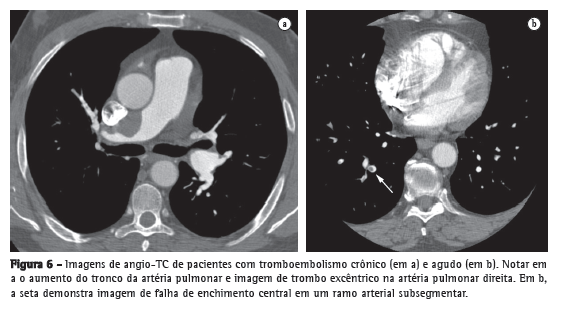

Bastante estudada, a angio-TC conquistou um amplo espaço na avaliação do TEP agudo, tornando-se um exame tão acurado quanto à angiografia pulmonar, mas desprovido do caráter invasivo. Uma série de estudos coloca a angio-TC como a primeira modalidade diagnóstica de imagem no estudo do TEP agudo.(34-36) O motivo está nas suas diversas vantagens: sua alta resolução permite a visualização de artérias e falhas de enchimento até a porção distal da vasculatura pulmonar, atingindo vasos subsegmentares de 2-3 mm (Figura 6); apresenta ótima concordância interobservador, bastante superior ao estudo cintilográfico; e sua sensibilidade é tão alta que um exame negativo pode indicar a suspensão de terapia anticoagulante com segurança.(37)

Deve-se ter cuidado, no entanto, com os perigos inerentes ao método. Fatores técnicos ou fisiopatológicos podem levar a interpretação de pseudofalhas de enchimento, trazendo resultados falso-positivos. Devem ser levados em consideração a possibilidade de artefato de movimento em pacientes taquipneicos, o intervalo de tempo entre a injeção do contraste e a aquisição da imagem e a ocorrência do fenômeno de vasoconstrição hipóxica em regiões mal aeradas. O aparecimento de tomógrafos de 64 canais abriu espaço para outro perigo: a possibilidade de excesso de resultados falso-positivos, que foi afastada em um estudo recente.(38)

Ao analisar com alta resolução a imagem do VD, a angio-TC pode figurar como um marcador na estratificação de risco de pacientes com TEP agudo, tradicionalmente feita por ecocardiografia.(39) Está bem estabelecido que o encontro de disfunção de VD determinada por ecocardiografia identifica um subgrupo de pacientes com alto risco para complicações, pior prognóstico e maior mortalidade. A reconstrução multiplanar da imagem do coração em quatro câmaras(40) ou a obtenção de cortes dos ventrículos em plano axial(41) permite o cálculo de uma razão simples: diâmetro diastólico do VD ÷ diâmetro diastólico do VE (razão VD/VE). O encontro de um valor > 0,90 correlaciona-se fortemente com a disfunção de VD determinada por ecocardiografia(42) e traz um potencial de custo-efetividade e de marcador prognóstico para a angio-TC. Em uma recente revisão sistemática analisando os resultados combinados de dois estudos de tomografia sobre o tema,(21) encontrou-se um risco relativo para a predição de morte de 2,3 (IC95%: 0,90-5,98) quando do achado de disfunção de VD. Em situação de TEP crônico distal, por outro lado, a angio-TC apresenta limitações, dando lugar à cintilografia de inalação/perfusão como exame de escolha.(43)